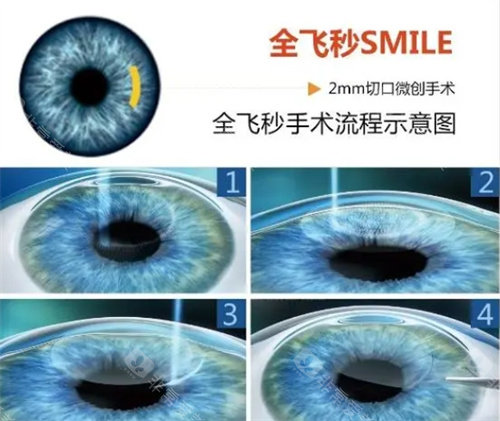

医院采用的手术方式主要有超声乳化白内障吸除术联合人工晶状体植入术等,这些手术方式具有切口小、改善快等优点。